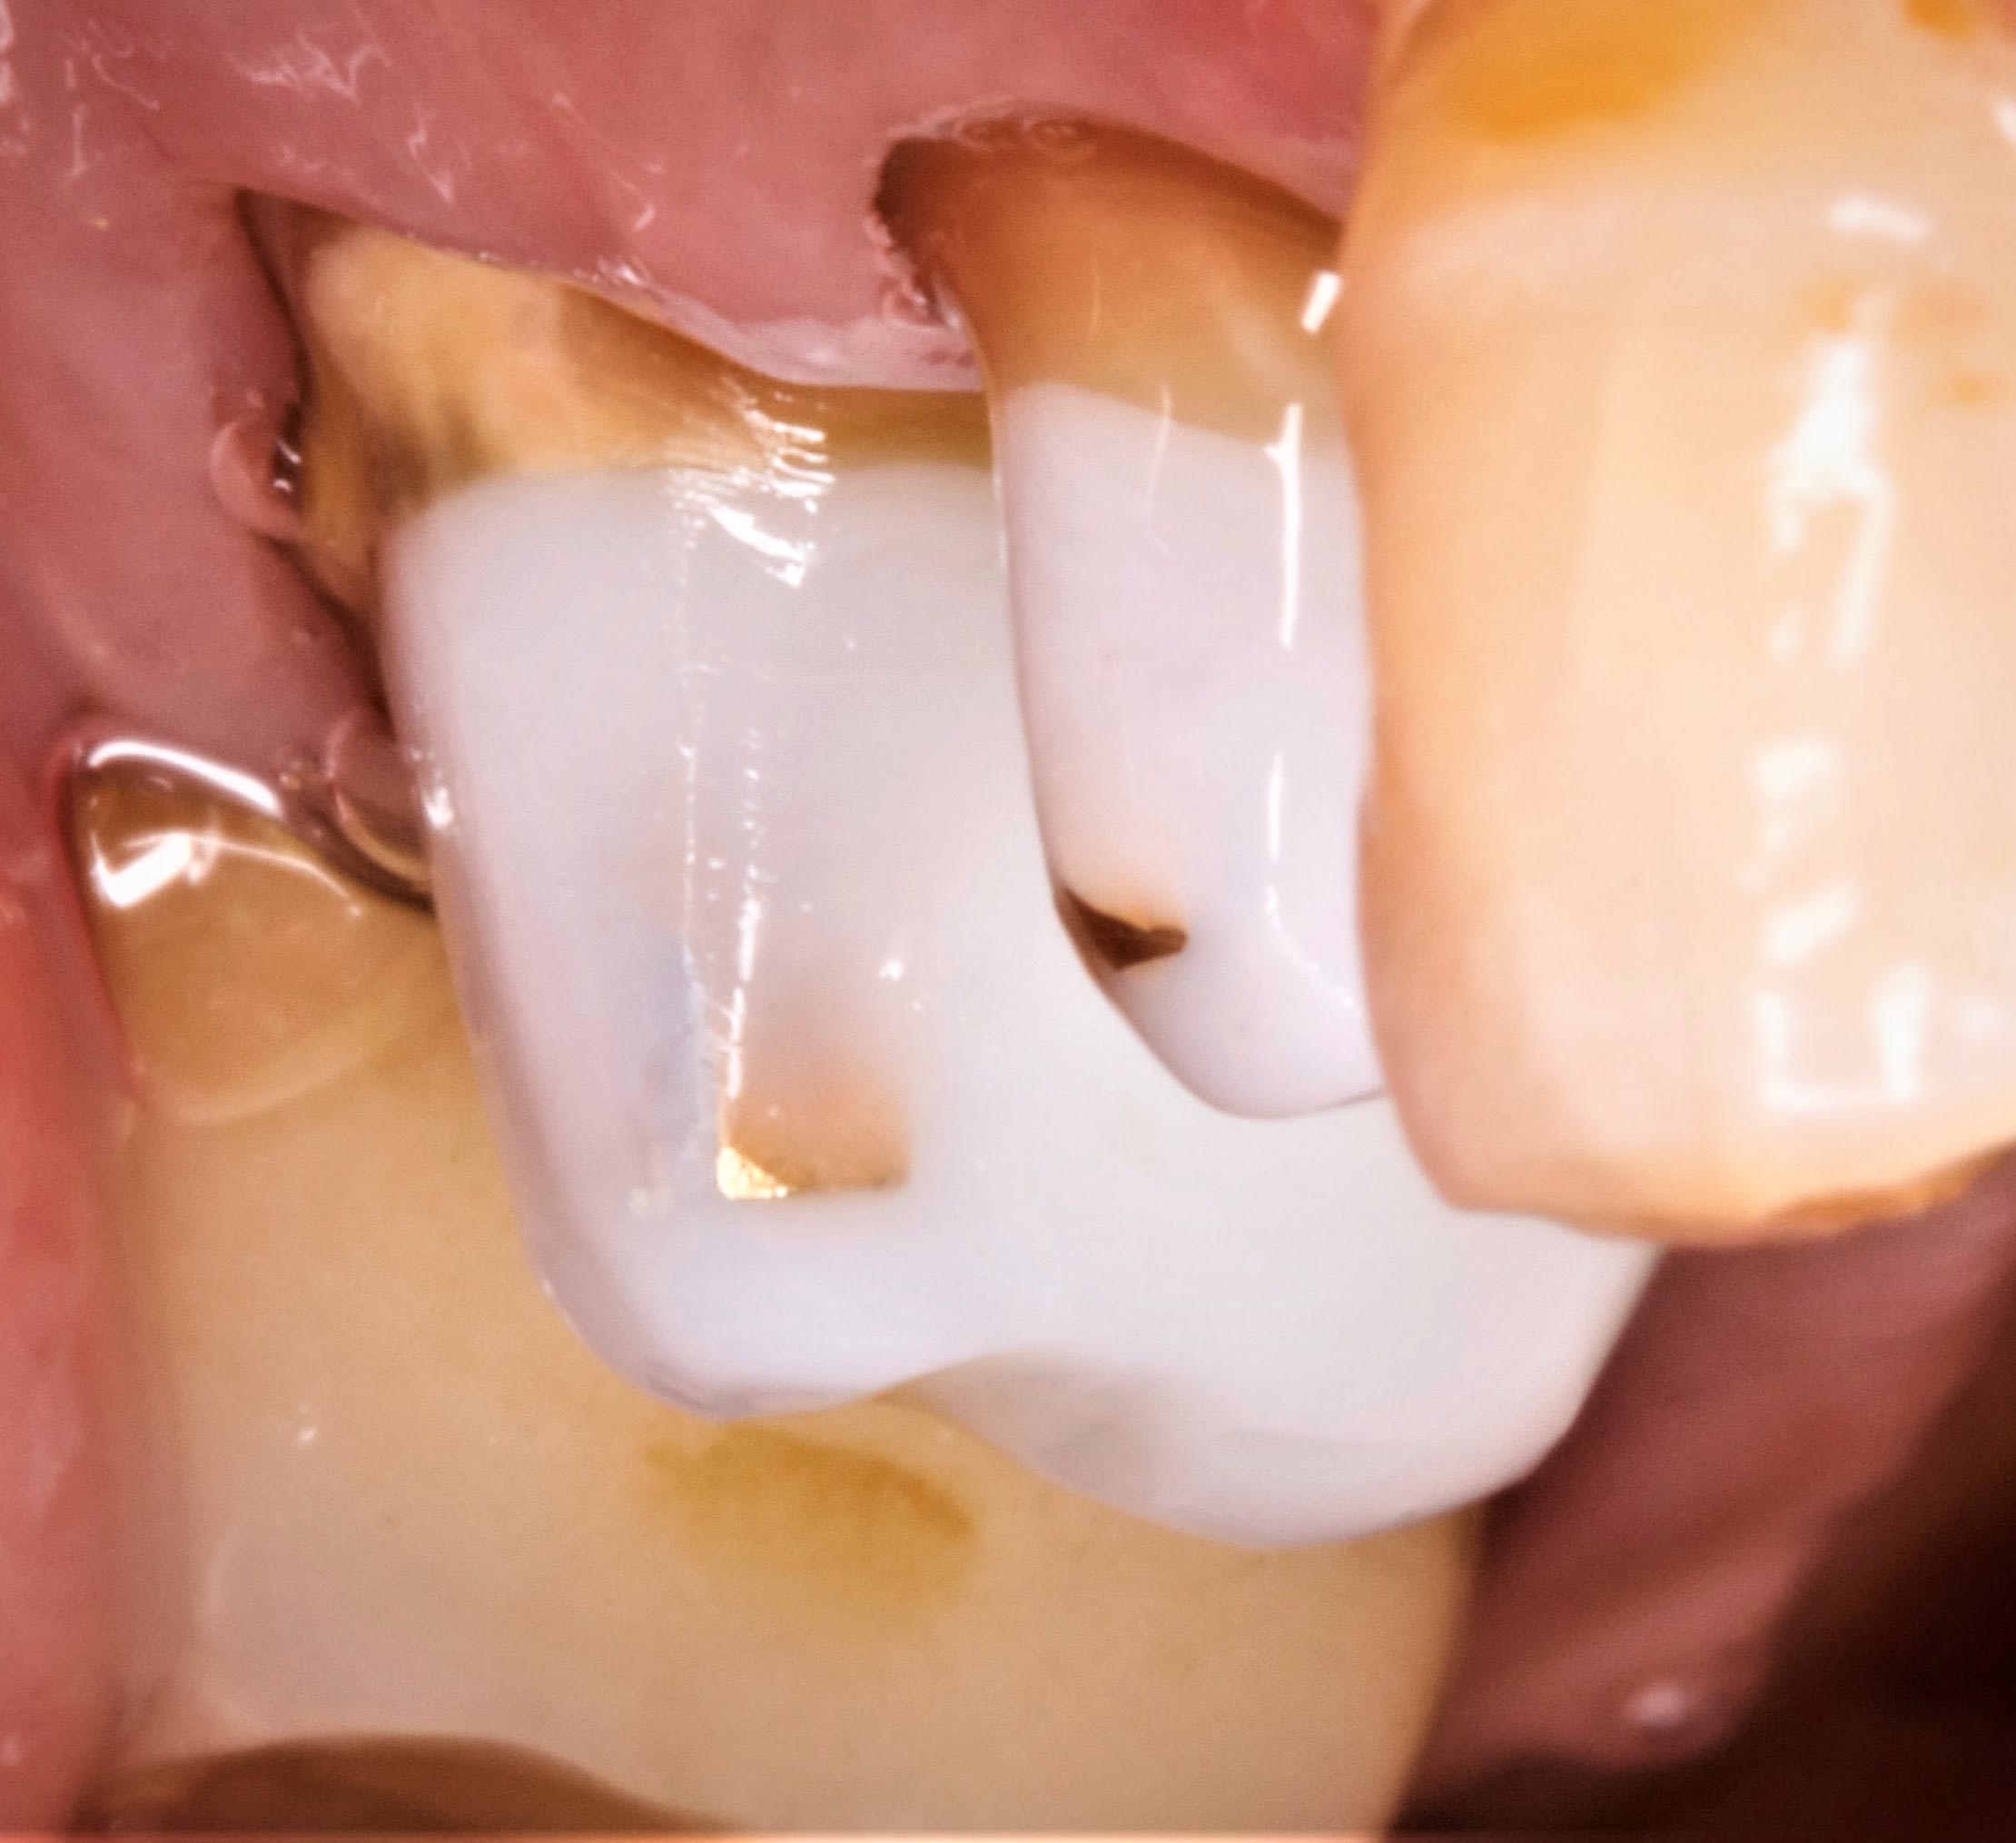

je fini le cas pour faire plaisir à Blaise .

donc aujourd’hui , , tjs sans prov , la gencive est impec .

y a plus qu a mettre .

mg 1897 bhqurf - Eugenol

mg 1898 baprff - Eugenol

il aurait pu personnaliser un peu ses ceram...

là encore ça va ç est du full @max à 110 e

Eh oui la gencive est belle quand on laisse la nature tranquille. Good job